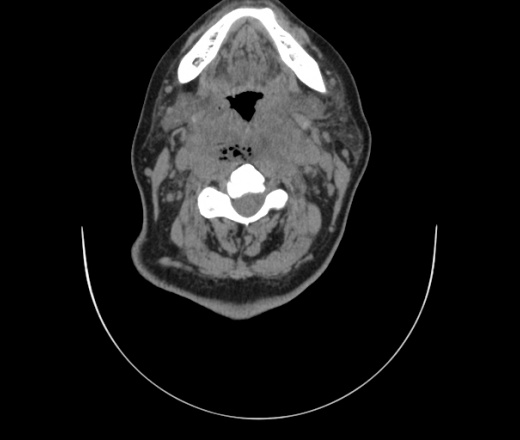

Женщина поступила в х/о спустя 4 дня после того как при употреблении карася подавилась костью.

Наличие газа в средостении на протяжении тел С2-С6 (медиастинальна эмфизема); рыбная кость на уровне тела С6.

При всем уважении, но говорить о медиастинальной эмфиземе, оценивая мягкие ткани шеи, как-то слишком резко. На мой взгляд, это ретрофарингеальное пространство.

Эвакуировали почти 100мл гноя. Но кость не смогли найти. Думаю что она даст дальнейшее ослоднение. Эндоскопически за черпалонадгортаной звязкой не смогли зайти в пищевод, все мягкие ткани отечные, просвет пищевода сдавлен. По всей видимости параэзофагеальная клетчака тоже задействована. Эмпиема, если ее можно так назвать, незнаю как правильно дошла до уровня яремной вырезки. Чем закончиться напишу. Ждем медиастинита.

Флегмона заглоточного пространства шеи, только операция, флегмоны вскрывают. Риск медиастинита.

Согласен с Вами; конечно, наличие газа в клетчатке ретрофарингеального пространства (затмение с опечаткой..). К сожалению, процесс "продвигается" к медиастиниту. Но почему никто, не отмечает наличие рыб. кости; или это для Всех очевидно?

Так вы уже отметили. Хотя ориентировал бы не скелетотопически, а на перстнечерпаловидный сустав.

Кость то мы сразу выявили, размеры где то 17*2мм, но ее так и не получается найти в этой каше